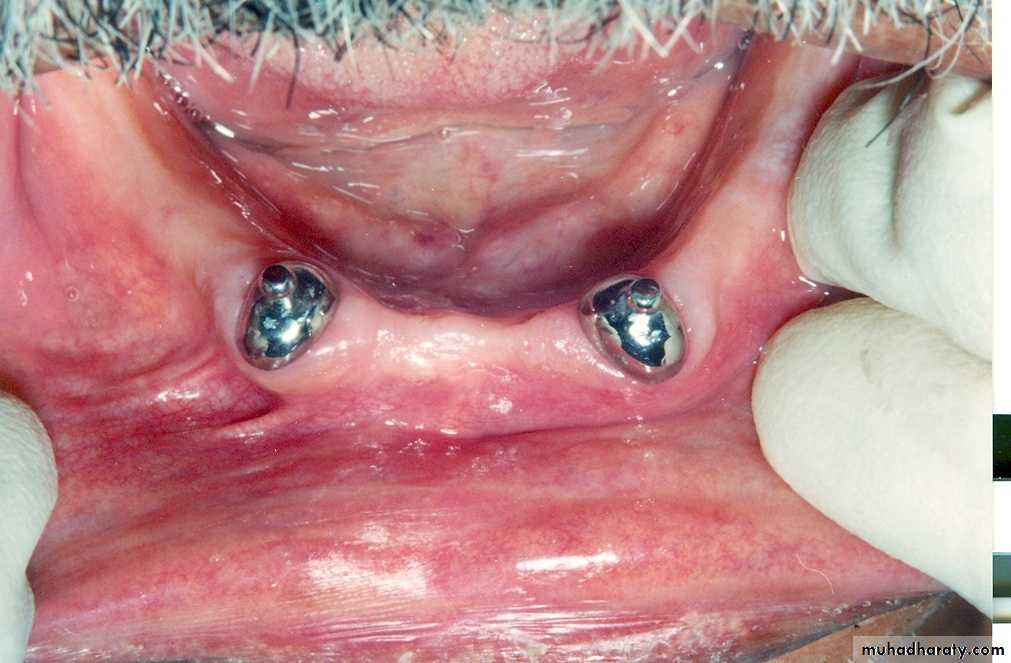

• ► Have applications for both root & implant supported prosthesis

* Chee & Donavan (1993), classified stud attachments into:Intra-radicular

Extra-radicular

* The male portion (patrix)

forms part of the denture base

and engages a special depression

within the root contour or implant

projects from the root surface

of the preparation or implant.

►Low caries index

►Adequate zone of attached gingivaRequirements of stud attachments

►Adequate periodontal support

►Controlled plaque & denture hygiene

►Adequate interocclusal clearance to allow for reasonable thickness of acrylic resin around the attachments.